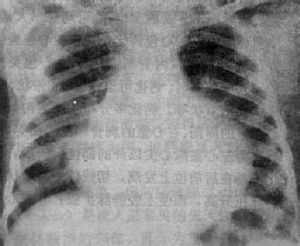

心臟示意圖心包積液是一種較常見的臨床表現尤其是在超聲心動圖成為心血管疾病的常規檢查方式之後,心包積液在病人中的檢出率明顯上升,可高達8.4%大部分心包積液由於量少而不出現臨床徵象。少數病人則由於大量積液而以心包積液成為突出的臨床表現。當心包積液持續數月以上時便構成慢性心包積液。導致慢性心包積液的病因有多種,大多與可累及心包的疾病有關。